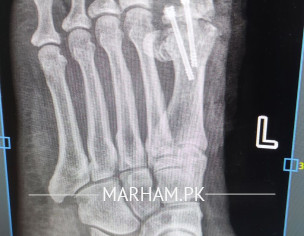

AoA, kindly ye meri mother ki xray report daikh kar bta dain k operation theek ho gya hai, X-ray main fracture nazar aa rha hai lekin, technician ny b kaha k fracture show ho rha hai kisi doctor ko dikha dain. shukria

Need following informations

1- Date of injury or weeks

2- XRay before Surgery

3- XRay just after surgery

4- XRay latest , you already shared

Regards

Osteotomy means cutting the bone to straighten it, usually to relieve pain or improve joint function. After the cut, the bone is held in place with plates, screws or pins while it heals. Most people need a period of limited weight‑bearing followed by physical therapy to rebuild strength and range of motion. Recovery can take several months, and the goal is to return to normal activities, but some patients may still need braces or activity adjustments. The procedure is common for knee, hip or foot problems, and outcomes are generally good when the surgeon’s plan matches the patient’s anatomy and the rehab is followed closely. If you’re considering it, talk to an orthopedic surgeon about your specific condition, the expected healing time, and any lifestyle changes that will help you recover fully.